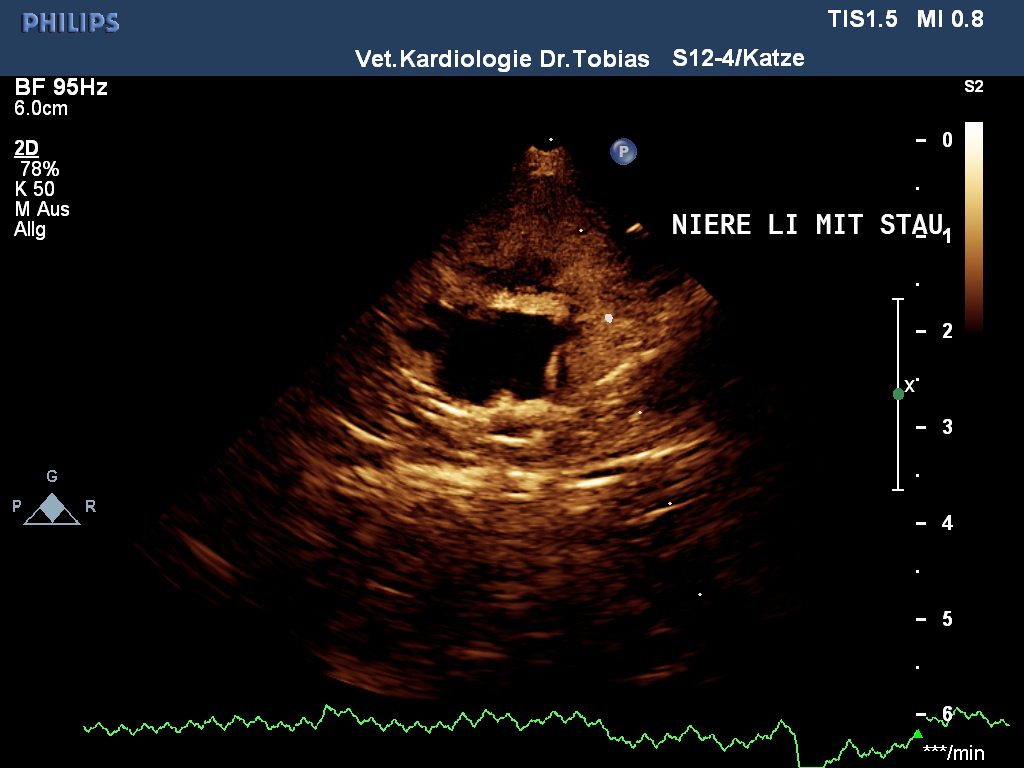

HCM- und Nieren-Schall September 2011

|

HCM normal

other diagnosis: Outburn Kardiomyopathie

aufgrund Niereninsuffizienz

sowie ggr. Mitralklappeninsuffizienz

age: 7y 9m

weight: 4.4 kg

IVSd: 3.1 mm

LVFWd: 3.3 mm

SAM: no

papillary muscles: normal

Dr.Tobias, Hannover